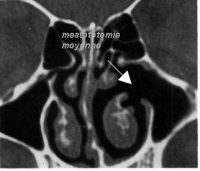

Méatotomie moyenne (ou maxillaire) – améliore le drainage des sinus situés derrière vos pommettes.

déterminerez si une méatotomie moyenne (ou maxillaire) est le meilleur traitement chirurgical pour votre infection chronique des sinus.Avant l'opération

Une méatotomie moyenne (ou maxillaire) est généralement réalisée en ambulatoire, ce qui veut dire que vous pouvez généralement rentrer chez vous le jour même. Faites en sorte qu'un ami ou un parent puisse vous ramener chez vous après l'opération.

Pendant l'opération

Une méatotomie moyenne (ou maxillaire) est généralement effectuée sous anesthésie générale. Elle dure 1 à 3 heures, selon votre état.

Pendant l'opération, l'ORL introduit un tube fin, appelé endoscope, dans votre nez. Ce tube est

muni à son extrémité d'une minuscule caméra et d'un dispositif lumineux, afin que le chirurgien puisse visualiser votre sinus maxillaire, l'ouverture du sinus maxillaire et sa zone de drainage (le complexe ostéoméatal). Puis de petits instruments chirurgicaux sont amenés jusqu'au site du problème.

Avec ces instruments, votre ORL libère vos sinus maxillaires. Cela améliore le drainage de vos sinus maxillaires et réduit les risques d'infection des sinus.